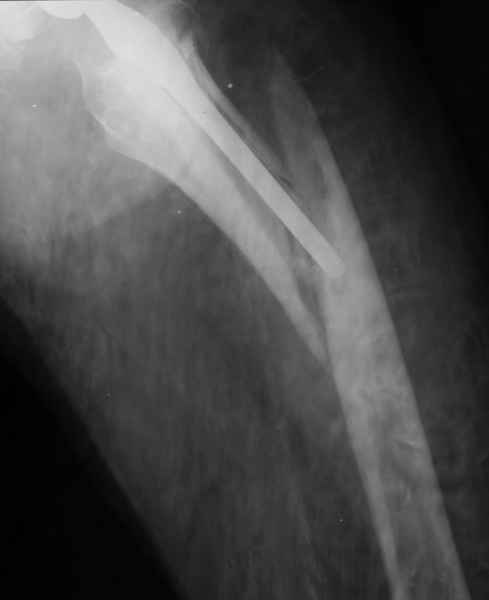

Весь проксимальный отдел бедренной кости ведь смещен относительно ножки эндопротеза? Значит менять ножку нужно. К тому же, если думать об удлинении ножки стержнем, место стыка получится как раз в области поперечной части перелома и о стабильности такой конструкции вряд ли можно будет думать. Так что - длинная ревизионная ножка с остеосинтезом. Может быть и серкляжей будет достаточно если перелом проксимальной части не оскольчатый (по снимкам не очень понятно).

Закрытый остеосинтез-удлинение ножки (подход далеко не общепринятый, и пока даже не общеизвестный)- наименее инвазивный вариант, который обеспечивает немедленное восстановление опороспособности. Конечно, хотелось бы, чтобы эта операция решила проблему окончательно, т.е. в

ближайшие годы других больших операций не потребовалось бы.

ножка просела немного (вопрос, много - это сколько?)перечисленные проблемы - не самое важное сейчас, на них можно закрыть глаза. Ножка явно нестабильна, проксимальный отломок с б/вертелом к гвоздю не прицепить, срастется ли он с ножкой

Начинать, на мой взгляд, надо с того, что перелом-то произошел из-за порочной (варусной) позиции ножки, не случись он сейчас, это произошло бы еще через полгода при более невинных обстоятельствах. Не видел конструкций , но дизайн ножки сильно напоминает цементную стандартную ножку Мюллера и, стало быть, наверное есть цементная мантия. В любом случае, на реинтеграцию этой ножки расчитывать нельзя. Поэтому, если нет общесоматических противопоказаний, нужно выполнять ревизионное эндопротезирование, оптимальный вариант - ножка Wagner Cone.

Это"Corail", так что никакой цементной мантии там нет.Непонятно с чего Вы решили,что ножка была установлена в "варусе"? Нынешнее ее положение, получено после травмы.